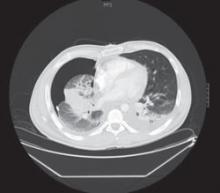

The chest x-ray revealed a massive right-sided pleural effusion resulting in a hemothorax, tense mediastinum, and partial collapse of the left lung. A CT scan (FIGURE 2) of the chest revealed a 5-cm mass in the right lung. Thoracocentesis was performed and 11 liters of pleural fluid were removed.

FIGURE 2

Mass in lung